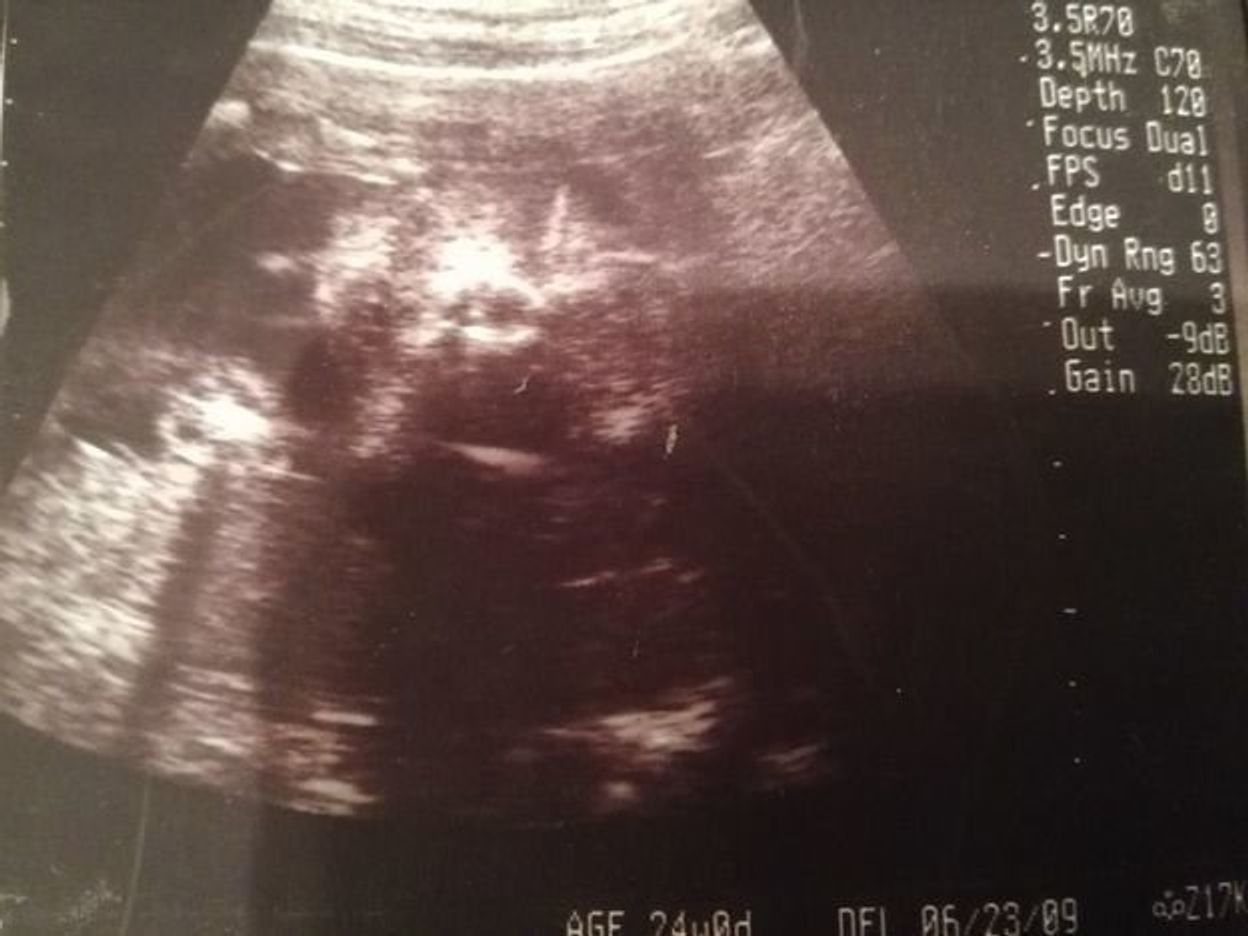

妊娠24週の検診 性別確定 浪費生活 いか 育児奮闘中

24週目・元気すぎて逆子になる 妊婦生活 日記 こんにちは、まめこです。 大分遅れていた妊娠記録も、妊娠7ヶ月の分に突入しました。 妊娠中期最後の月ですね。 2人目の妊娠中って、1人目の時と比べるとすごーーくあっという間に過ぎてしまった印象逆子とは 赤ちゃんは、お母さんのお腹の中(子宮内)で頭が下を向いています(頭位)。しかし、時々、 頭が上向き になってしまう赤ちゃんがいます。 この状態のことを「 逆子 」といいます。 医学用語では「 骨盤位 (こつばんい)」と呼んでいます。 通常、逆子は妊娠28週目までに赤ちゃんの頭 こんにちは! 妊活・妊娠情報サイト「ももいろファミリー」のももです。 現在妊娠7ヶ月、お腹の赤ちゃんは26週です。 妊娠中期の逆子診断 直近の妊婦健診に行ったところ、エコー検査でなんと 逆子ですね〜。

妊娠24週には激しい胎動を感じることも。 逆子は心配しなくても大丈夫 激しい胎動を感じることも多いでしょう。 赤ちゃんの骨格が発達し、お腹の中で上手に動きまわるようになるからです。 赤ちゃんの足や肩などが膀胱の近くにあると、痛みを感じる妊娠16週目安定期に突入もつわりはぶり返し胎動も感じない日々 妊娠17週目エコーで性別が確定する時期!胎動はどんな感じ? 妊娠22週目胎動が急に感じなくなった?急激な体重増加にも注意!! 妊娠24週目胎動を激しく強く感じる頃!